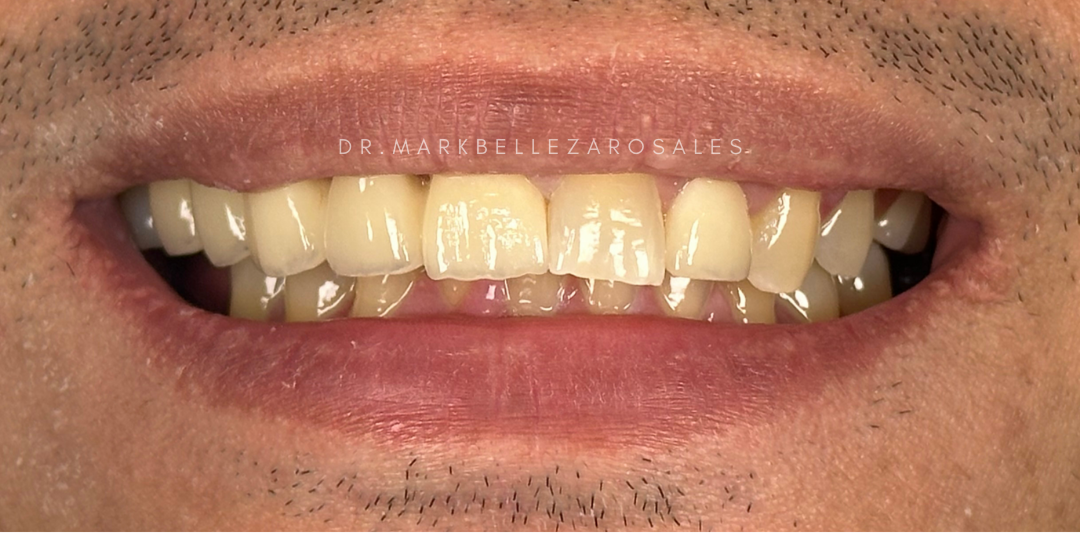

A porcelain fused metal bridge is a fixed dental restoration used to replace missing teeth by combining a strong metal framework with a porcelain exterior. It offers durability and support while maintaining a natural tooth-like appearance for effective chewing and a balanced smile.